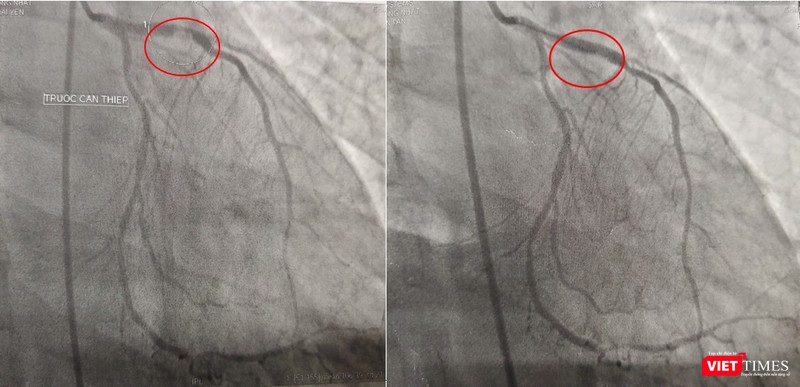

Kết quả chụp DSA mạch vành: bán tắc đoạn gần LAD do huyết khối, can thiệp và đặt stent cho bệnh nhân

Kết quả chụp mạch máu tại phòng DSA cho thấy bệnh nhân bị đột quỵ não do huyết khối gây ra tắc hoàn toàn một nhánh động mạch lớn của não, đồng thời, còn phát bệnh nhân bị bệnh cả 3 nhánh động mạch vành nặng với huyết khối gây tắc gần hoàn nhánh động mạch lớn nuôi trái tim LAD (nhánh động mạch liên thất trước), 2 nhánh còn lại có một nhánh hẹp nặng, một nhánh bị tắc hoàn toàn mạn tính đã lâu.